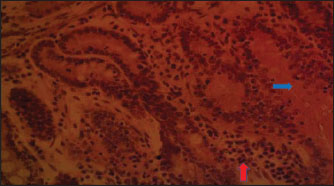

Fig. 5. (LMM) Section of the intestine showing moderated necrosis of Crept of Lieberkühn (blue arrow) and mucosal (arrow head) epithelial cells, with mild infiltration of inflammatory cells (red arrow) (x400; H & E).

In the NLM shown in Figure 1, the mucosal lining was complete, with the Lieberkühn villi and crypts properly arranged. The epithelial layer, largely composed of absorptive enterocytes and goblet cells, was well preserved and did not show cellular erosion or necrosis (An et al., 2022). The lamina propria appeared to be free of inflammatory infiltrations, and the make-up was not atrophied or distorted, indicating a healthy mucosal barrier and optimum operational capacity (France and Turner, 2017). The TDLM (Fig. 2) had effects that showed cellular disintegration of the Lieberkühn crypts, signifying epithelial rejuvenation (Liu et al., 2019). At the same time, mucosal epithelial inner layer necrosis, shown by disturbed cellular structure and cytoplasmic degradation, suggests a distorted mucosal barrier that may amplify absorptivity, poor nutrient assimilation, and increased susceptibility to enteric pathogens (Chistiakov et al., 2014; De Medina et al., 2014). These observed changes can be due to the secondary metabolites like saponins, alkaloids, phenolics, and tannins present in Tithonia diversifolia, which are known to cause cytotoxic, anti-proliferative, and membrane-disrupting activities in the GIT tract when taken unprocessed (Abdelsalam and Fathi, 2023). These observations demonstrate the need for detoxification, quantification, and probably fermentation when incorporating TDLM into the diet of local rabbits (Abd-Elghany et al., 2021). Although TDLM provides a good source of nutritious and phytogenic benefits, its raw inclusion must be controlled to avoid compromising gut integrity and performance (Sugiharto et al, no date). In the observed PBLM in Figure 3, the necrosis in the crypt of Lieberkühn shows disturbance of the proliferative region crucial for epithelial regeneration and intestinal homeostasis (Chistiakov et al., 2014). Impairment of the crypts affects enterocyte production, which may cause weakened absorptive and digestive effectiveness in the small intestine (Buckley and Turner, 2018). Concurrently, mucosal epithelial cell degeneration and necrosis show intestinal barrier failure, increasing the danger of luminal antigen translocation and mucosal susceptibility (An et al., 2022). The permeation of inflammatory cells, mainly lymphocytes and macrophages, demonstrates a limited immune response that may be a reaction to epithelial injury caused by phytochemicals in Parkia biglobosa leaves (Franz et al., 2019). These bioactive constituents possess antioxidant and antimicrobial properties and may cause cytotoxic effects at high levels of inclusion in unprocessed form. Tannins and saponins can tamper with membrane integrity, modify gut microflora, and trigger mucosal irritation (De Medina et al., 2014). These effects are consistent with the inflammatory and degenerative changes observed in the duodenal mucosa (Chistiakov et al., 2014; De Medina et al., 2014). The observed necrosis in the crypt that controls epithelial cell production and mucosal renewal in rabbits fed SNLM indicates weakened cellular turnover (Buckley and Turner, 2018). Moreover, the loss of mucosal epithelial cells’ integrity shows that the absorptive and protective barrier is compromised, which is crucial for nutrient uptake and host protection (Liu et al., 2022). The infiltration of inflammatory cells, principally comprising lymphocytes and plasma cells, into the lamina propria, as shown in Figure 4, demonstrates an ongoing immune response that may have been prompted by mucosal or antigenic disturbance from biologically active compounds in Synedrella nodiflora. If the concentration is not regulated, this can lead to a cytotoxic or pro-inflammatory effect on the mucosa of the GIT (Jha et al., 2019). Specifically, saponins are known to disrupt membranes and increase gut penetrability, possibly leading to reactionary inflammation and epithelial damage (Ohimain et al., 2020). Necrosis of the Lieberkühn crypt observed in the LMM (Fig. 5) and damage to the mucosal epithelial cells affect the intestinal epithelium, compromising absorptive and secretory activities crucial for gut health (Buckley and Turner, 2018). This pattern is consistent with that observed in other leaf meals; however, the infiltration of inflammatory cells appeared mild, suggesting a moderate but continuous controlled immune response, possibly to clear away cellular fragments and restore mucosal integrity (Chistiakov et al., 2014; De Medina et al., 2014). This trend aligns with subacute intestinal damage, where soreness is present but not distressing, enabling mucosal recovery if the injurious stimuli are removed (France and Turner, 2017; An et al., 2022).